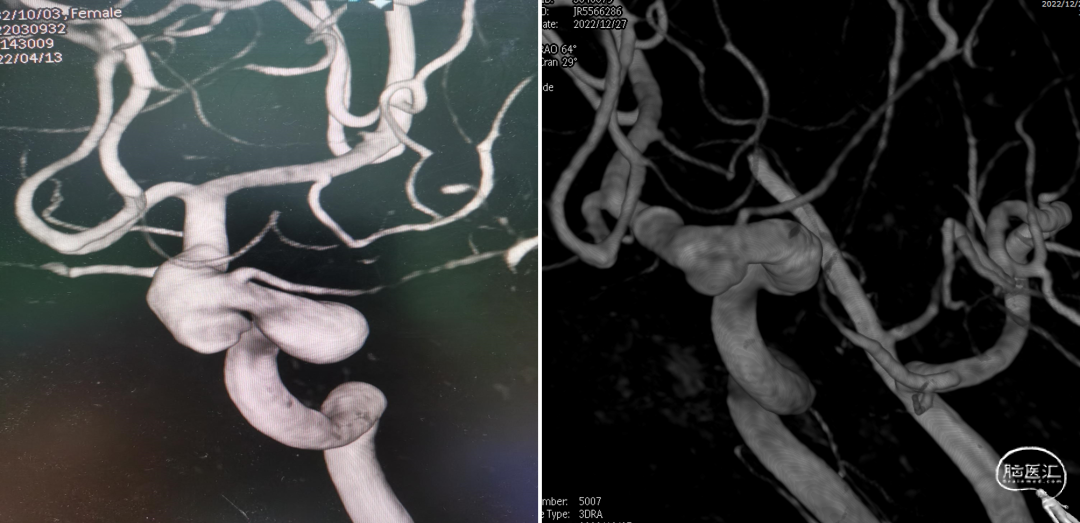

全脑血管造影(2022-04-13)

右颈内动脉3D重建(海绵窦段宽径7.2mm)

左颈内动脉3D重建图像(眼段宽径7.8mm)

左颈内动脉3D重建图像(海绵窦段宽径6.5mm)

术后复查右颈内动脉3D重建

术后3D重建

术前、术后3D图像对比